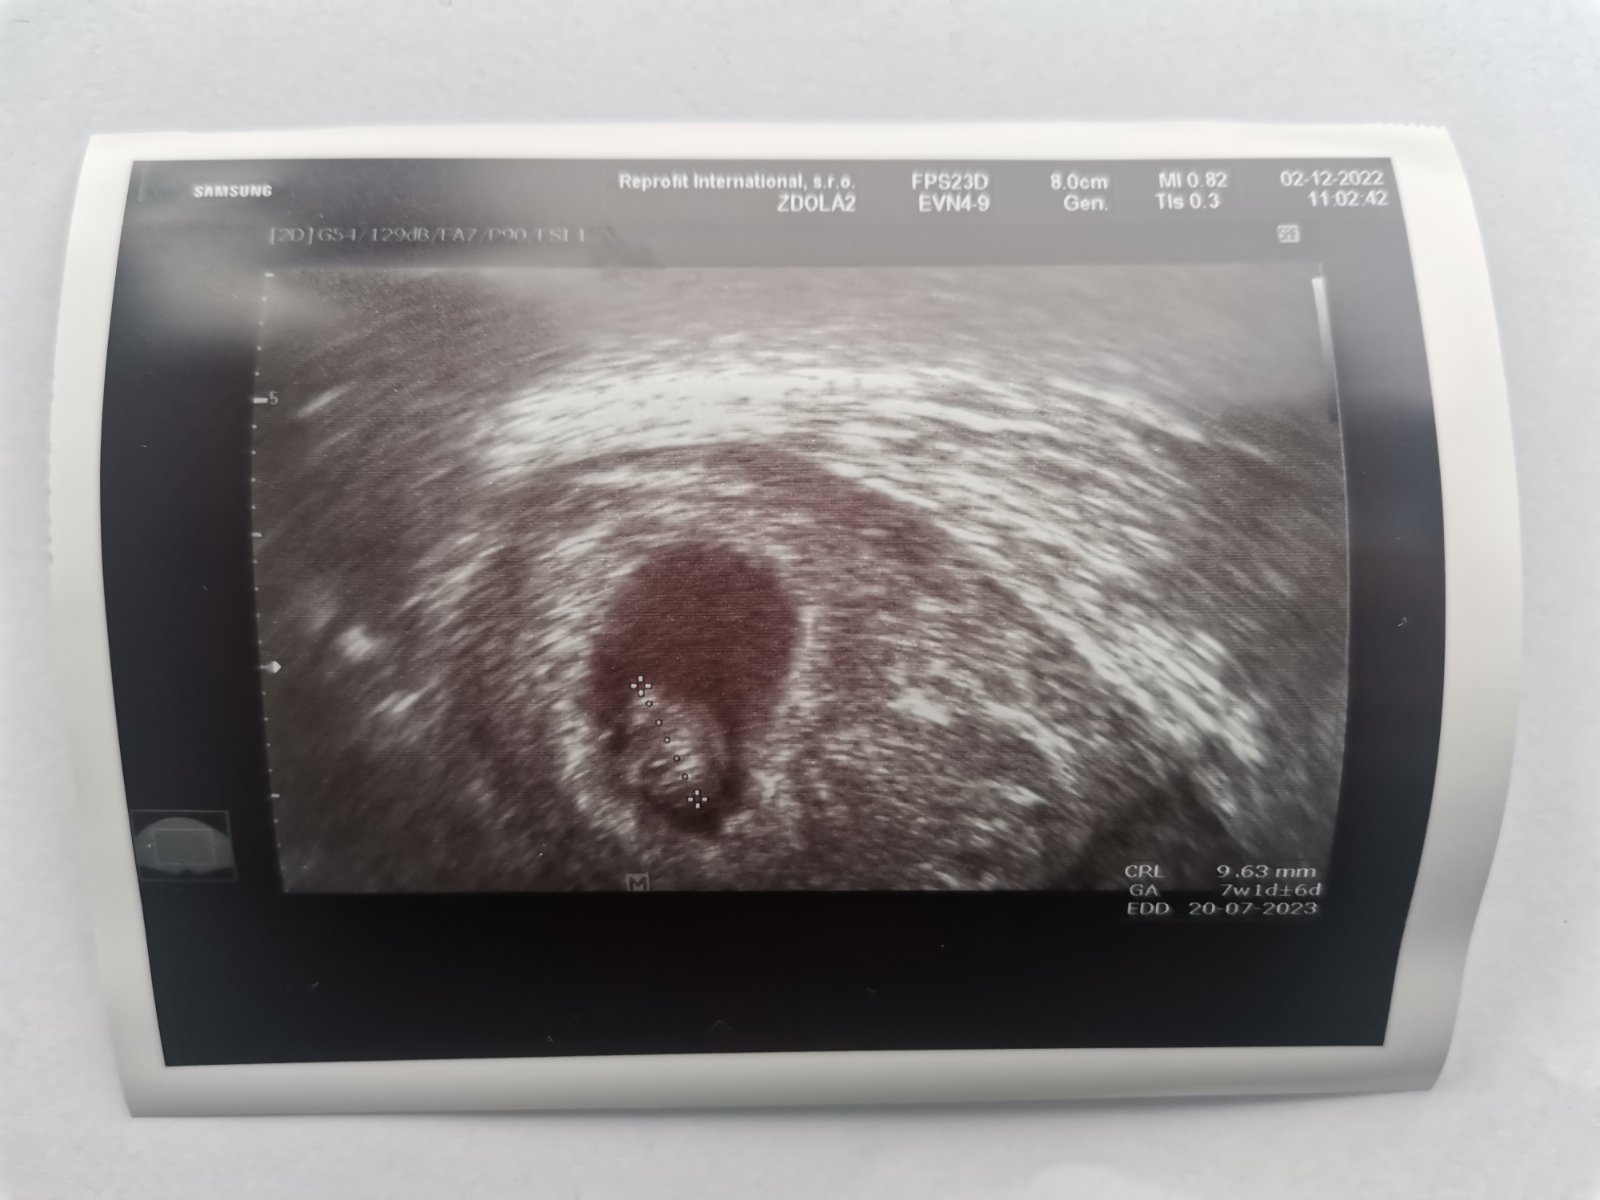

Ahojte dievčatá, dnes 14 DPT, HCG 1329, na sone už bolo vidno krásnu bodku o veľkosti 3 mm ❤ Každej jednej z vás prajem, aby zažila tento pocit, držím vám moc moc palce, nech to tu pokračuje pozitívnymi správami ❤